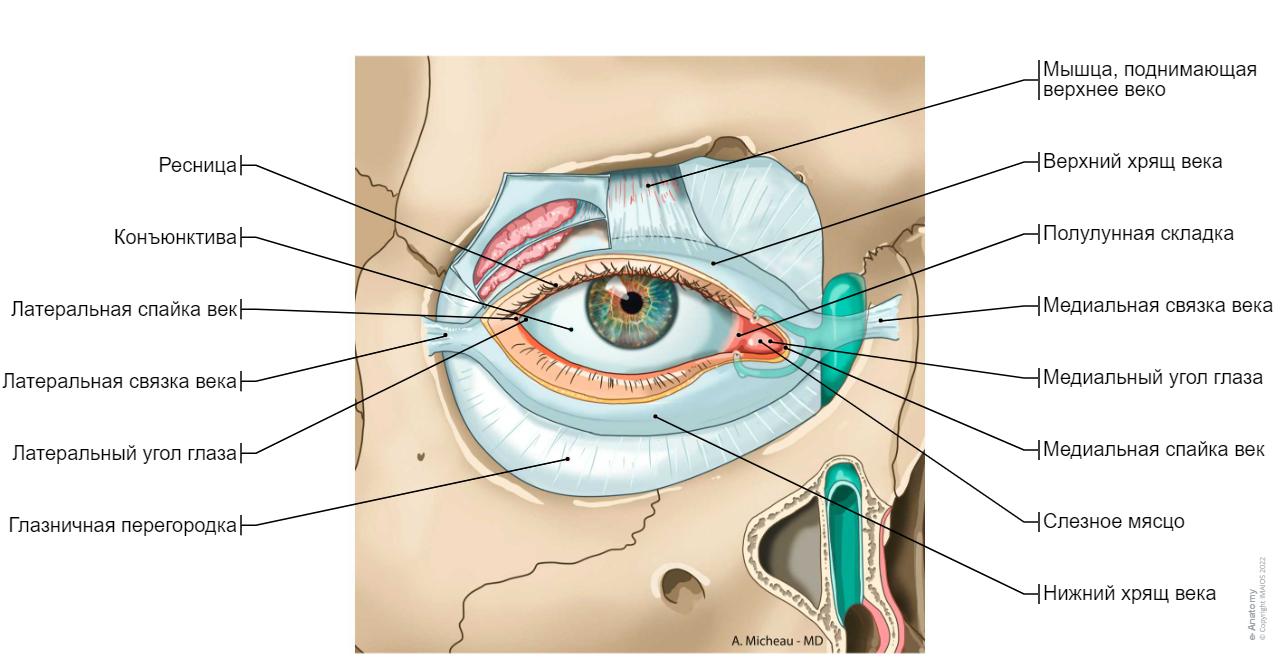

КТ-графики и изображение строения глаза